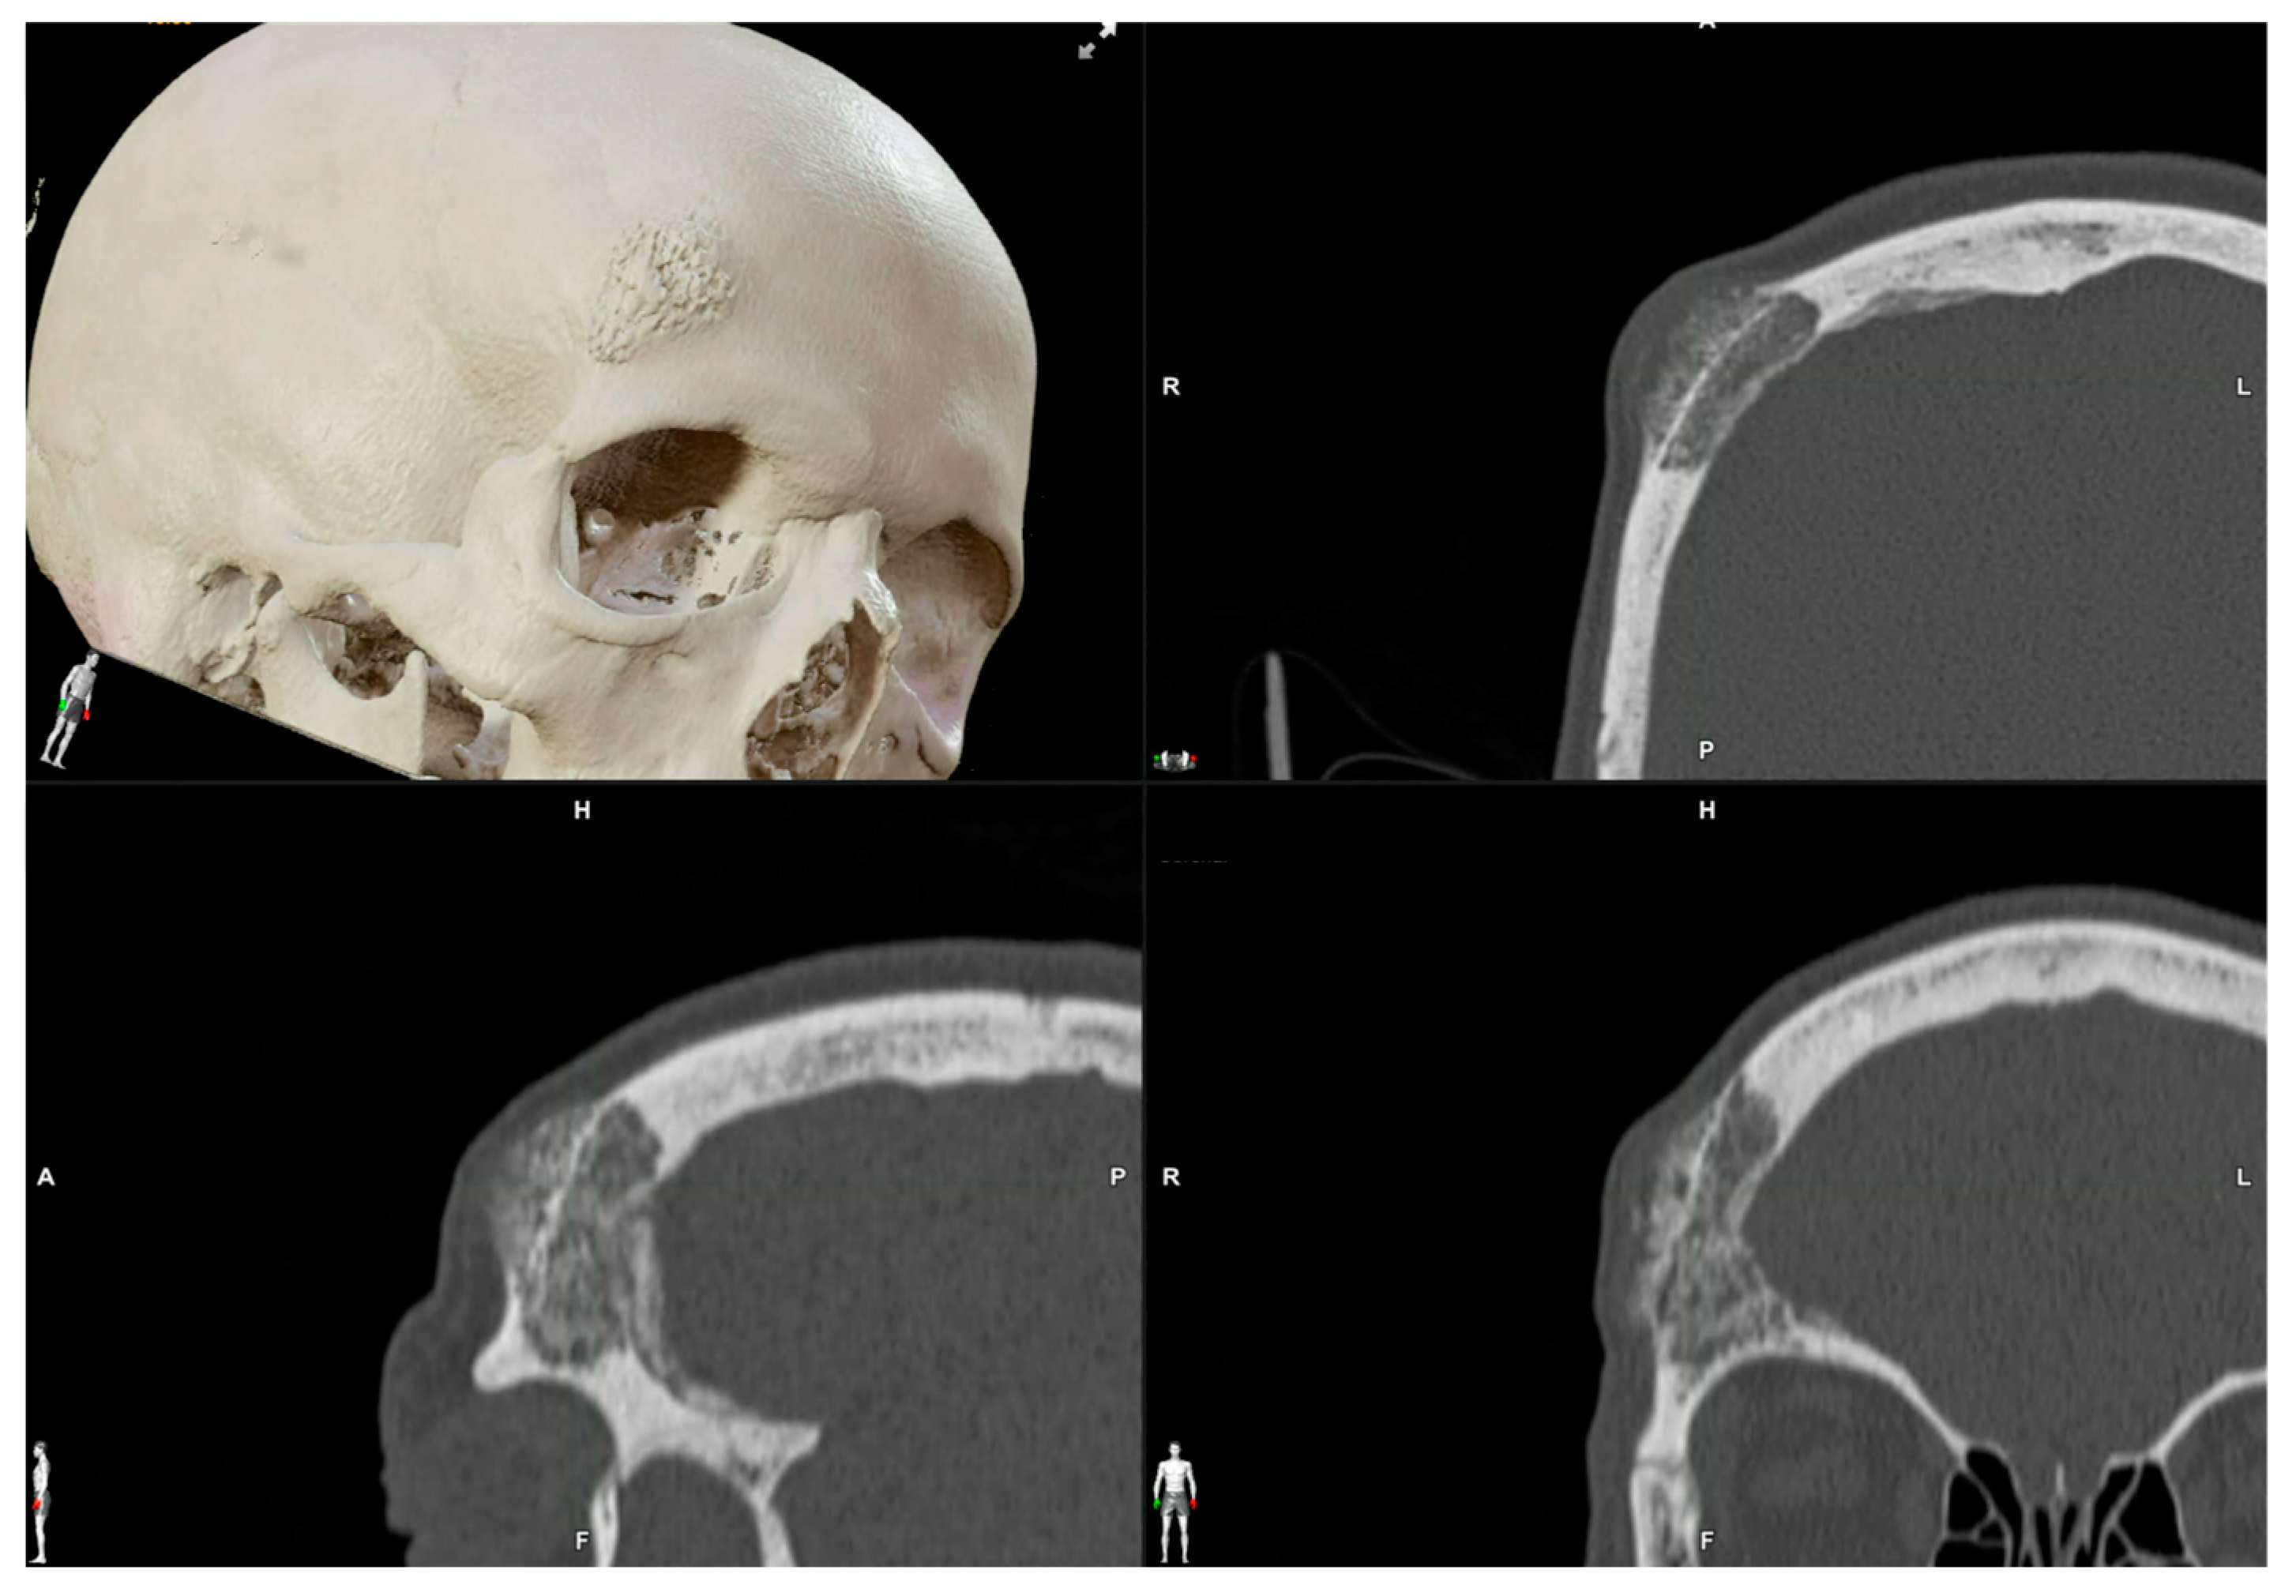

| 1 | 53/F | L/25 mm | Y | 4 mo | Dystopia | N | CT, MRI | Supraorbital rim, orbital roof | Intraosseous venous malformation | - | Resection + reconstruction | Y | Y | 1st, 2nd, 3rd | Coronal | Y | Piezoelectric device | N | PEEK prosthesis | 7 y/N |

| 2 | 54/F | R/33 mm | Y | 9 y | N | Y | CT, MRI | Frontal bone, orbital roof | Intraosseous venous malformation | - | Resection + reconstruction | Y | Y | 1st, 2nd, 3rd | Coronal | Y | Piezoelectric device | N | PEEK prosthesis | 6 y/N |